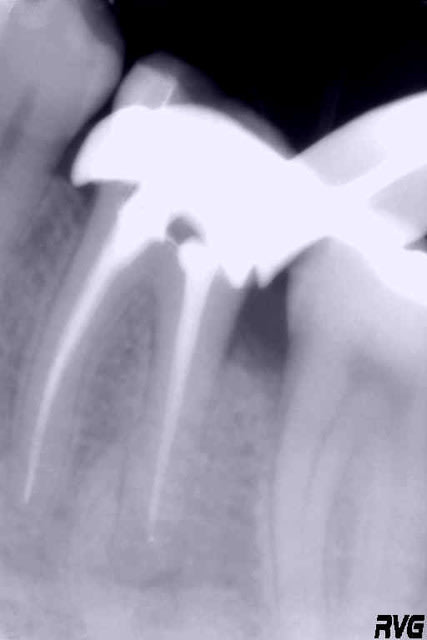

Pour exemple, l'endo de l'heure précédente est jointe...

Mark, le temps entre les deux clichés est celui qui sépare les deux messages ; le localisateur me signale l'apex sur les deux racines mésiales, mais effectivement pas sur la racine distale que je n'ai pu explorer plus avant...obturation par thermocompactage, petites sensibilités sur les trois canaux lors de l'obturation...

Un delta apical obturé avec thermocondensation